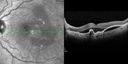

69 y.o Hispanic Female The left eye started with treatment for wet AMD September 2012. She has been getting monthly Eylea treatment. The last treatment was 2/11/14. She is due for a treatment soon. She did have some Kenalog with one of her recent treatments. VA OD: cc20/20-1 PHNI NccJ1 OS: cc20/80-3 PHNI IOP: TP OD: 16 OS: 14

Polypoidal Choroidal Vasculopathy with Pulsating ICG polyp left eye629 views00000